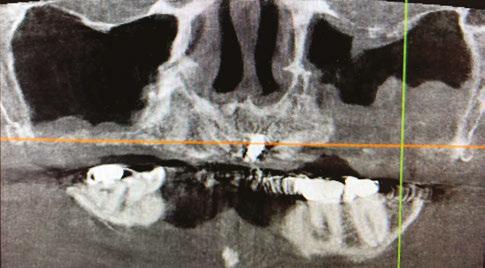

Figure 1 (left): Radiographic example of soft D4 bone. Figure 2 (right): Radiographic example of more dense D1/D2 bone

Evaluation of hard tissue quantity and quality (Figures 1 and 2) is a key diagnostic factor when determining potential sites for sufficient primary stability. The implant surgeon needs to be able to evaluate a patient’s CBCT to locate areas of hard tissue for dental implants to be placed in a prosthetically driven, mechanically fixed, and biologically stable position. This is done by identifying and evaluating the patient-specific variations of common anatomical structures such as the maxillary sinus, nasal aperture, neurovascular canals, and the bone density (classified as D1, D2, D3, or D4 bone by Misch). Common areas of bone used for full-arch immediately loaded implants in the maxilla include: the alveolar ridge and basal bone apical to extraction sockets, palatal